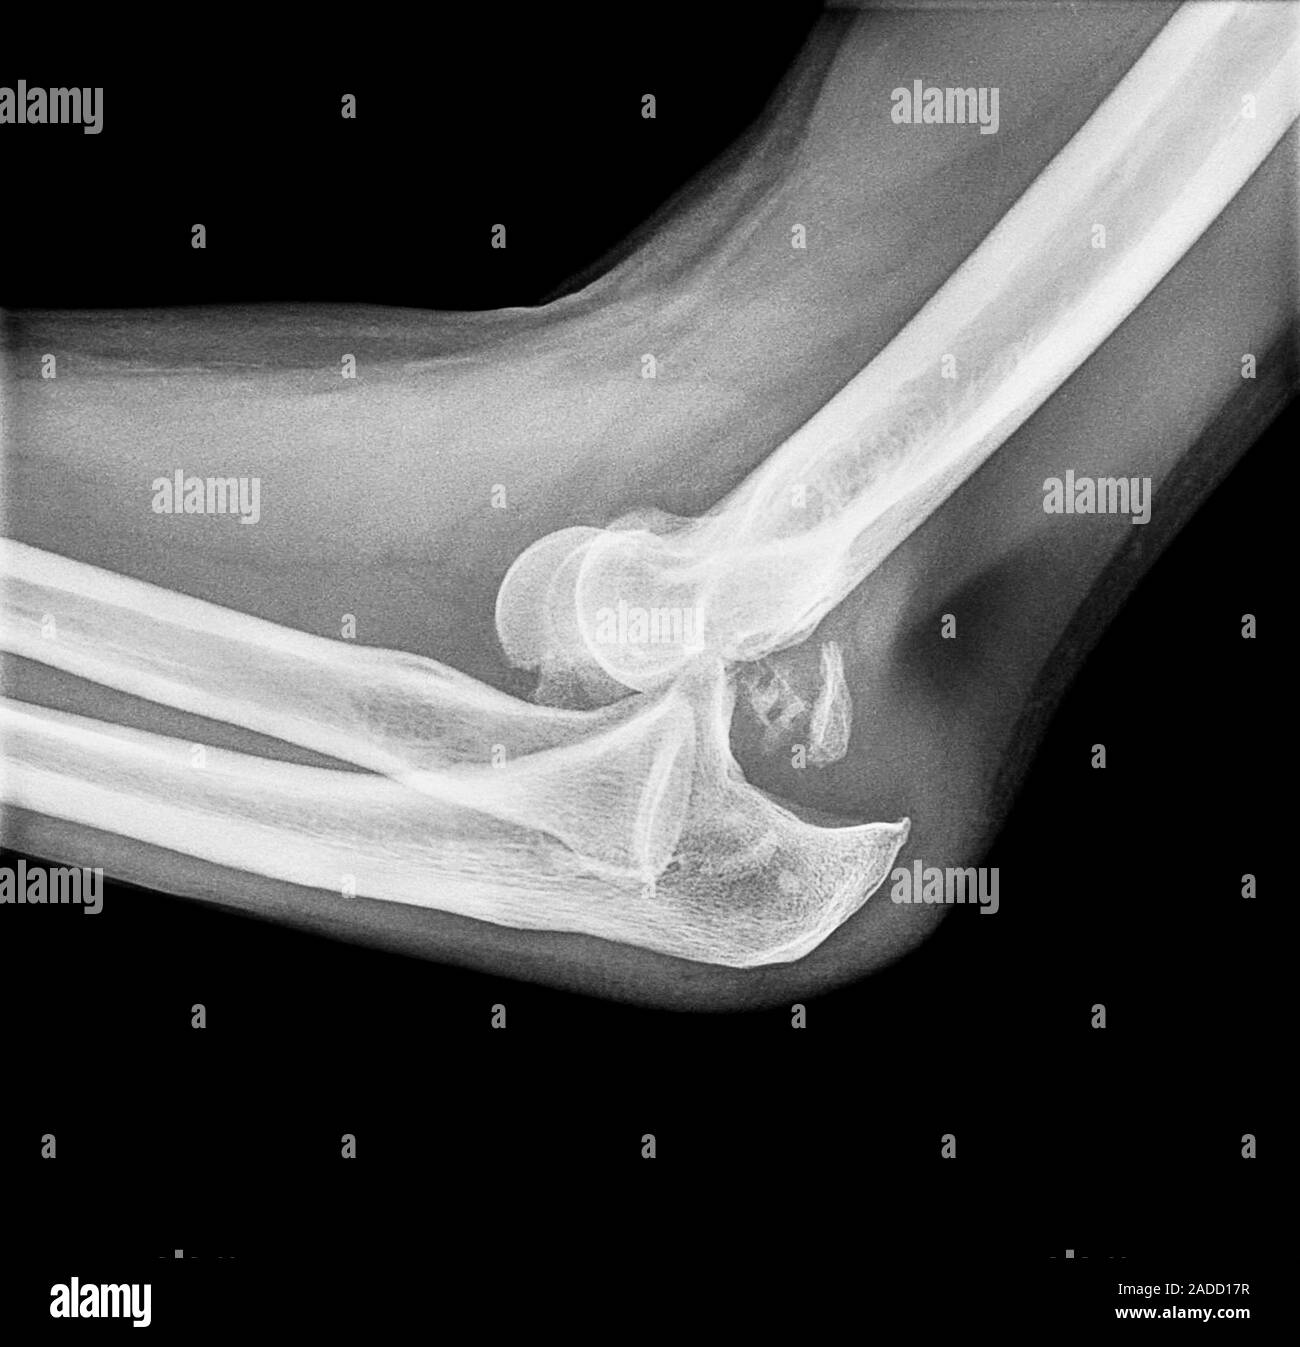

From www.alamy.com

Dislocated elbow. Xray of the elbow of a 58yearold man with a What Do They Do For Dislocated Elbow Simple dislocations occur when there is no fracture. When dealing with an elbow dislocation, avoiding common mistakes is crucial for a successful recovery. Elbow dislocations can be separated into simple and complex. A complex one does have broken. Signs and symptoms of a dislocated elbow include a visible deformity, pain, and swelling. A dislocated elbow occurs when the elbow bones. What Do They Do For Dislocated Elbow.